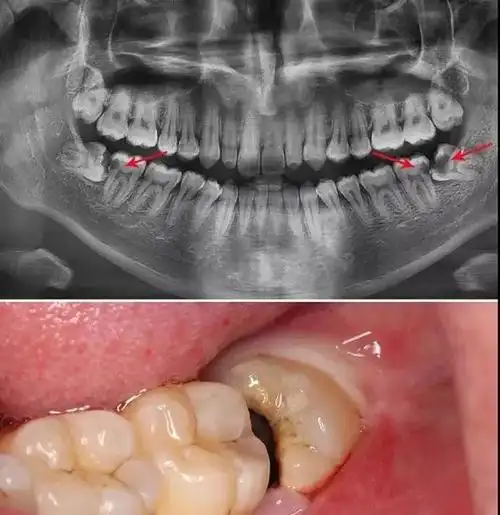

今天,小编要和大家讲的是智齿冠周炎,它是指智齿(第三磨牙)萌出不全或

智齿,也称为第三磨牙,通常在青少年期萌出,位于口腔最后方.